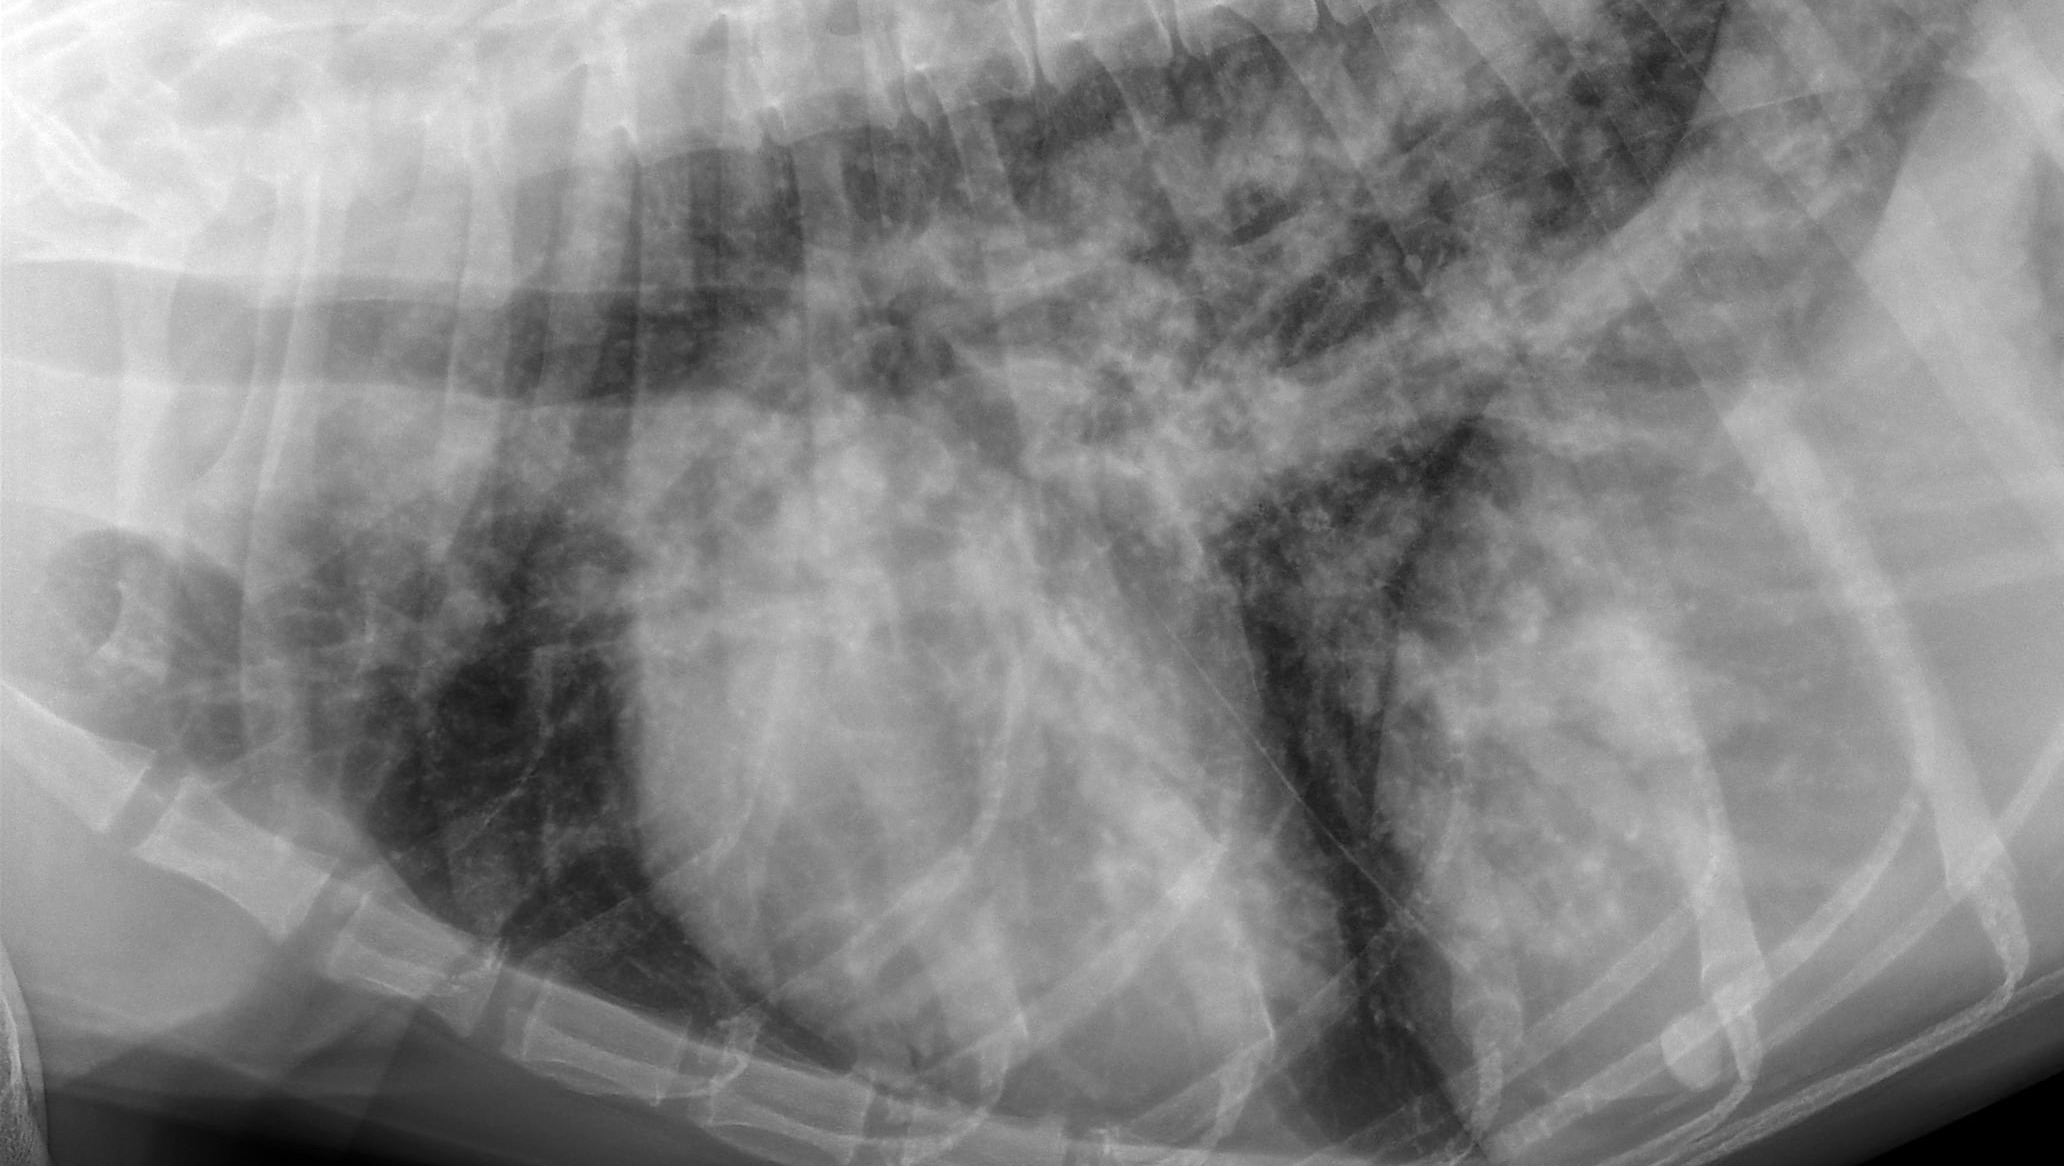

Blastomycosis looks like a snow storm in the lungs which is evident in Daisy's first x-ray. Daisy's prognosis was a 50% survival rate but so far she is still hanging in there. She is 3 months into Blasto treatment with anti-fungal medication and 6 months into heartworm slow kill.